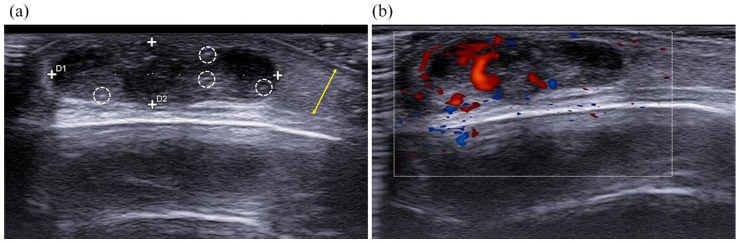

毛瘤是一种罕见的良性肿瘤,起源于头发皮层细胞,在儿童中典型表现为生长缓慢的蓝红色,表面和坚硬的肿块。多发性毛瘤可与基因突变和综合征相关,最常见的是Rubinstein-Taybi综合征、Gardner综合征、肌强直性营养不良症、Turner综合征和Sotos综合征。超声检查可以确定肿瘤的特征,评估深层结构的受累情况,并制定治疗计划。毛囊基质瘤表现出一些独特的超声特征,有助于其诊断,在超声上可视为卵形复杂肿块。毛瘤的并发症和恶性转化已被描述为可能的肿瘤发展,并建议手术切除。我们报告一例罕见的17岁女性智力残疾和小头畸形患者,超声检查显示头颈部有多发毛瘤。患者的综合征特征和基因测试导致鲁宾斯坦-泰比综合征的诊断。我们还关注了鲁宾斯坦-泰比综合征患者毛瘤基质瘤与基因突变之间的关系。

Pilomatricoma is a rare benign neoplasm originating from hair cortex cells and typically manifests in children as a slow-growing bluish-red, superficial and firm mass. Multiple pilomatricomas can be associated with genetic mutations and syndromic disorders, most commonly with Rubinstein-Taybi syndrome, Gardner syndrome, myotonic dystrophy, Turner syndrome, and Sotos syndrome. Ultrasound examination allows this tumor to be characterized, to assess the involvement of deeper structures and to plan treatment. Pilomatricoma shows some distinctive ultrasonographic features that aid in its diagnosis and it may be seen on ultrasound as an ovoid complex mass. Complications and malignant transformation of pilomatricomas have been described as a possible tumor evolution, and surgical resection is recommended. We present a rare case of a 17-year-old female patient with intellectual disability and microcephaly, and with the evidence of multiple pilomatricomas in the head-neck region on ultrasound examination. The syndromic features of the patient and genetic tests led to a diagnosis of Rubinstein-Taybi syndrome. We also focused on the association between pilomatricomas and genetic mutations in patients with Rubinstein-Taybi syndrome.